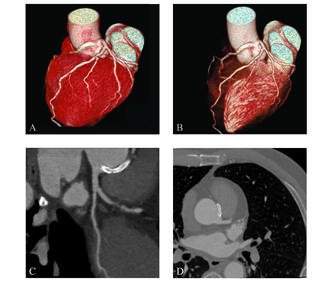

A 69-year-old man with unstable angina underwent coronary angiography showing no lesion in the left coronary artery and critical stenosis in the proximal right coronary artery arising from the left sinus of Valsalva.